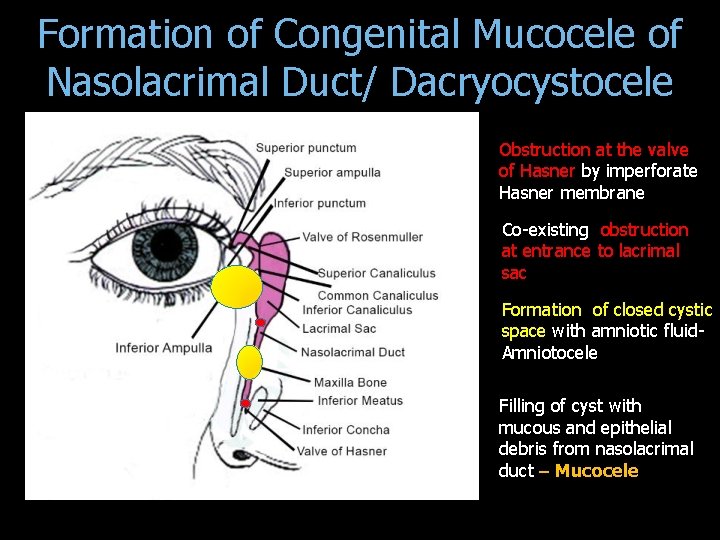

Formation of Congenital Mucocele of Nasolacrimal Duct/ Dacryocystocele Obstruction at the valve of Hasner by imperforate Hasner membrane Co-existing obstruction at entrance to lacrimal sac Formation of closed cystic space with amniotic fluid- Amniotocele Filling of cyst with mucous and epithelial debris from nasolacrimal duct – Mucocele